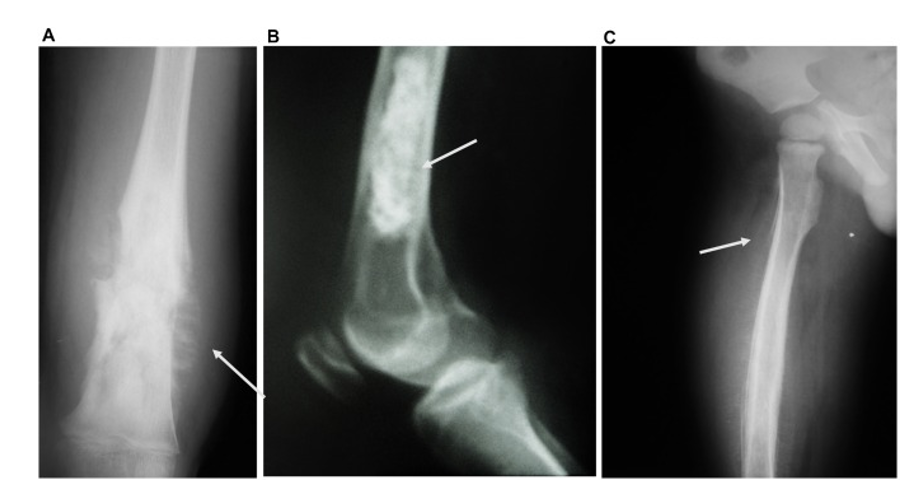

X-ray merupakan modalitas awal dan paling mudah untuk diakses. Temuan khas meliputi lesi litik atau blastik, destruksi korteks, dan reaksi periosteal agresif seperti sunburst appearance atau Codman triangle. Selain itu, dapat ditemukan massa jaringan lunak dan pembentukan matriks osteoid.